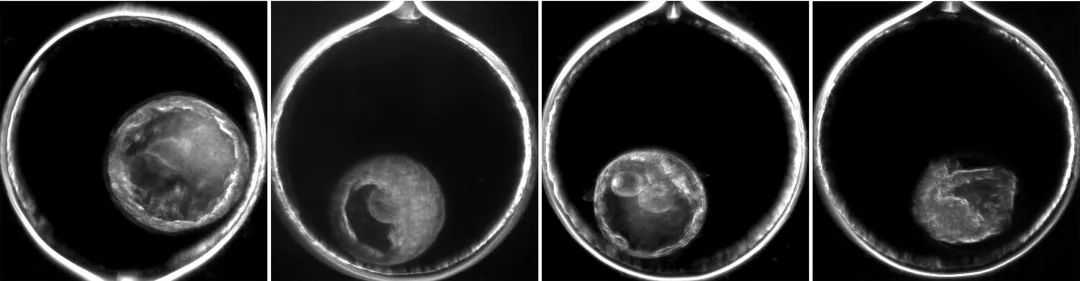

细胞分裂的生物学过程(如图所示)在识别胚胎内的遗传异常中起着重要作用。

Chavez和他的研究小组利用先进的延时成像和单细胞测序技术,精确追踪恒河猴嵌合体胚胎的发育过程,发现嵌合体与细胞分裂和卵裂球排斥(blastomereexclusion)两个生物过程之间的独特关系。

在子宫内和IVF后,由受精卵分裂形成的卵裂球(blastomeres),可能会分解成小块的细胞碎片(cellularfragments)。

“我们发现,卵裂球和它们的碎片都可以在胚胎中充当‘垃圾箱’的角色。随着携带DNA的细胞分裂和/或碎片化,胚胎似乎自然地识别哪些卵裂球有基因异常,并阻止它们进一步发展,”Chavez说道,“在胚胎植入子宫的阶段,这些异常细胞或DNA已经明显被排除在胚胎的其他部分之外。这表明,不完美的胚胎可以考虑用于IVF移植,并可能在子宫内存活。”